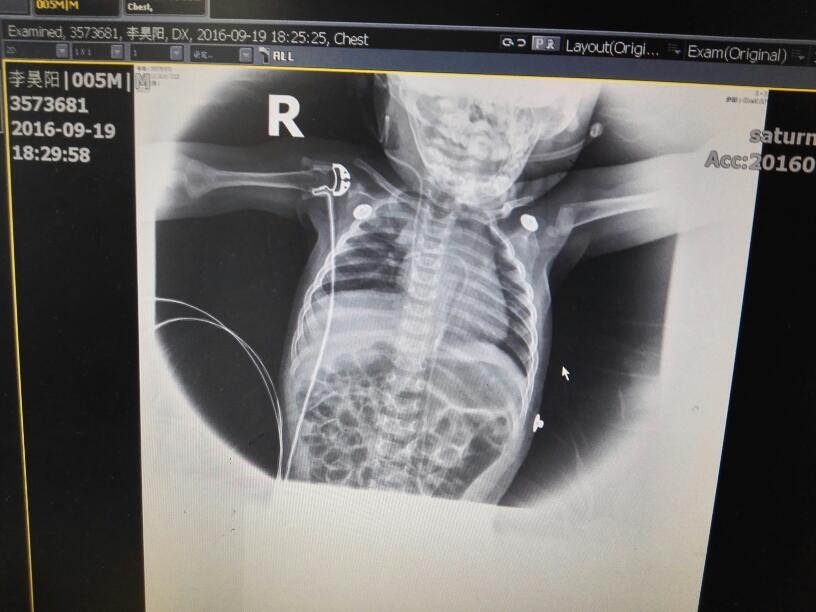

六个月宝宝心包积液,在温州附二育英儿童医院查了一个月没查出原因!!查的结果身体状况都是健康的,宝宝能吃能睡能玩,但积液还是每天二十毫升左右流着,让家人痛苦宝宝难受,求全国哪家或是认识的人帮忙介绍下,我不想让我的宝宝插着引流管生活,这一个月插了二次了,宝宝太小要全麻微创手术太危险了!!先谢谢大家了!!